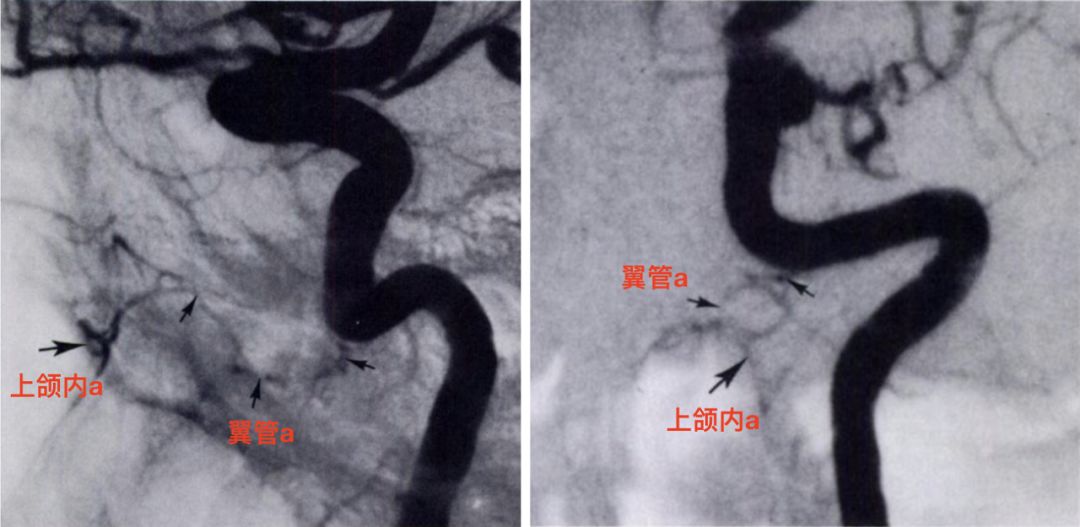

颈内动脉侧位(左)和正位(右)显示翼管动脉(小箭)发自颈内动脉岩段,向前通过翼管,与上颌内动脉远端(大箭)吻合(Osborn, 1980)。